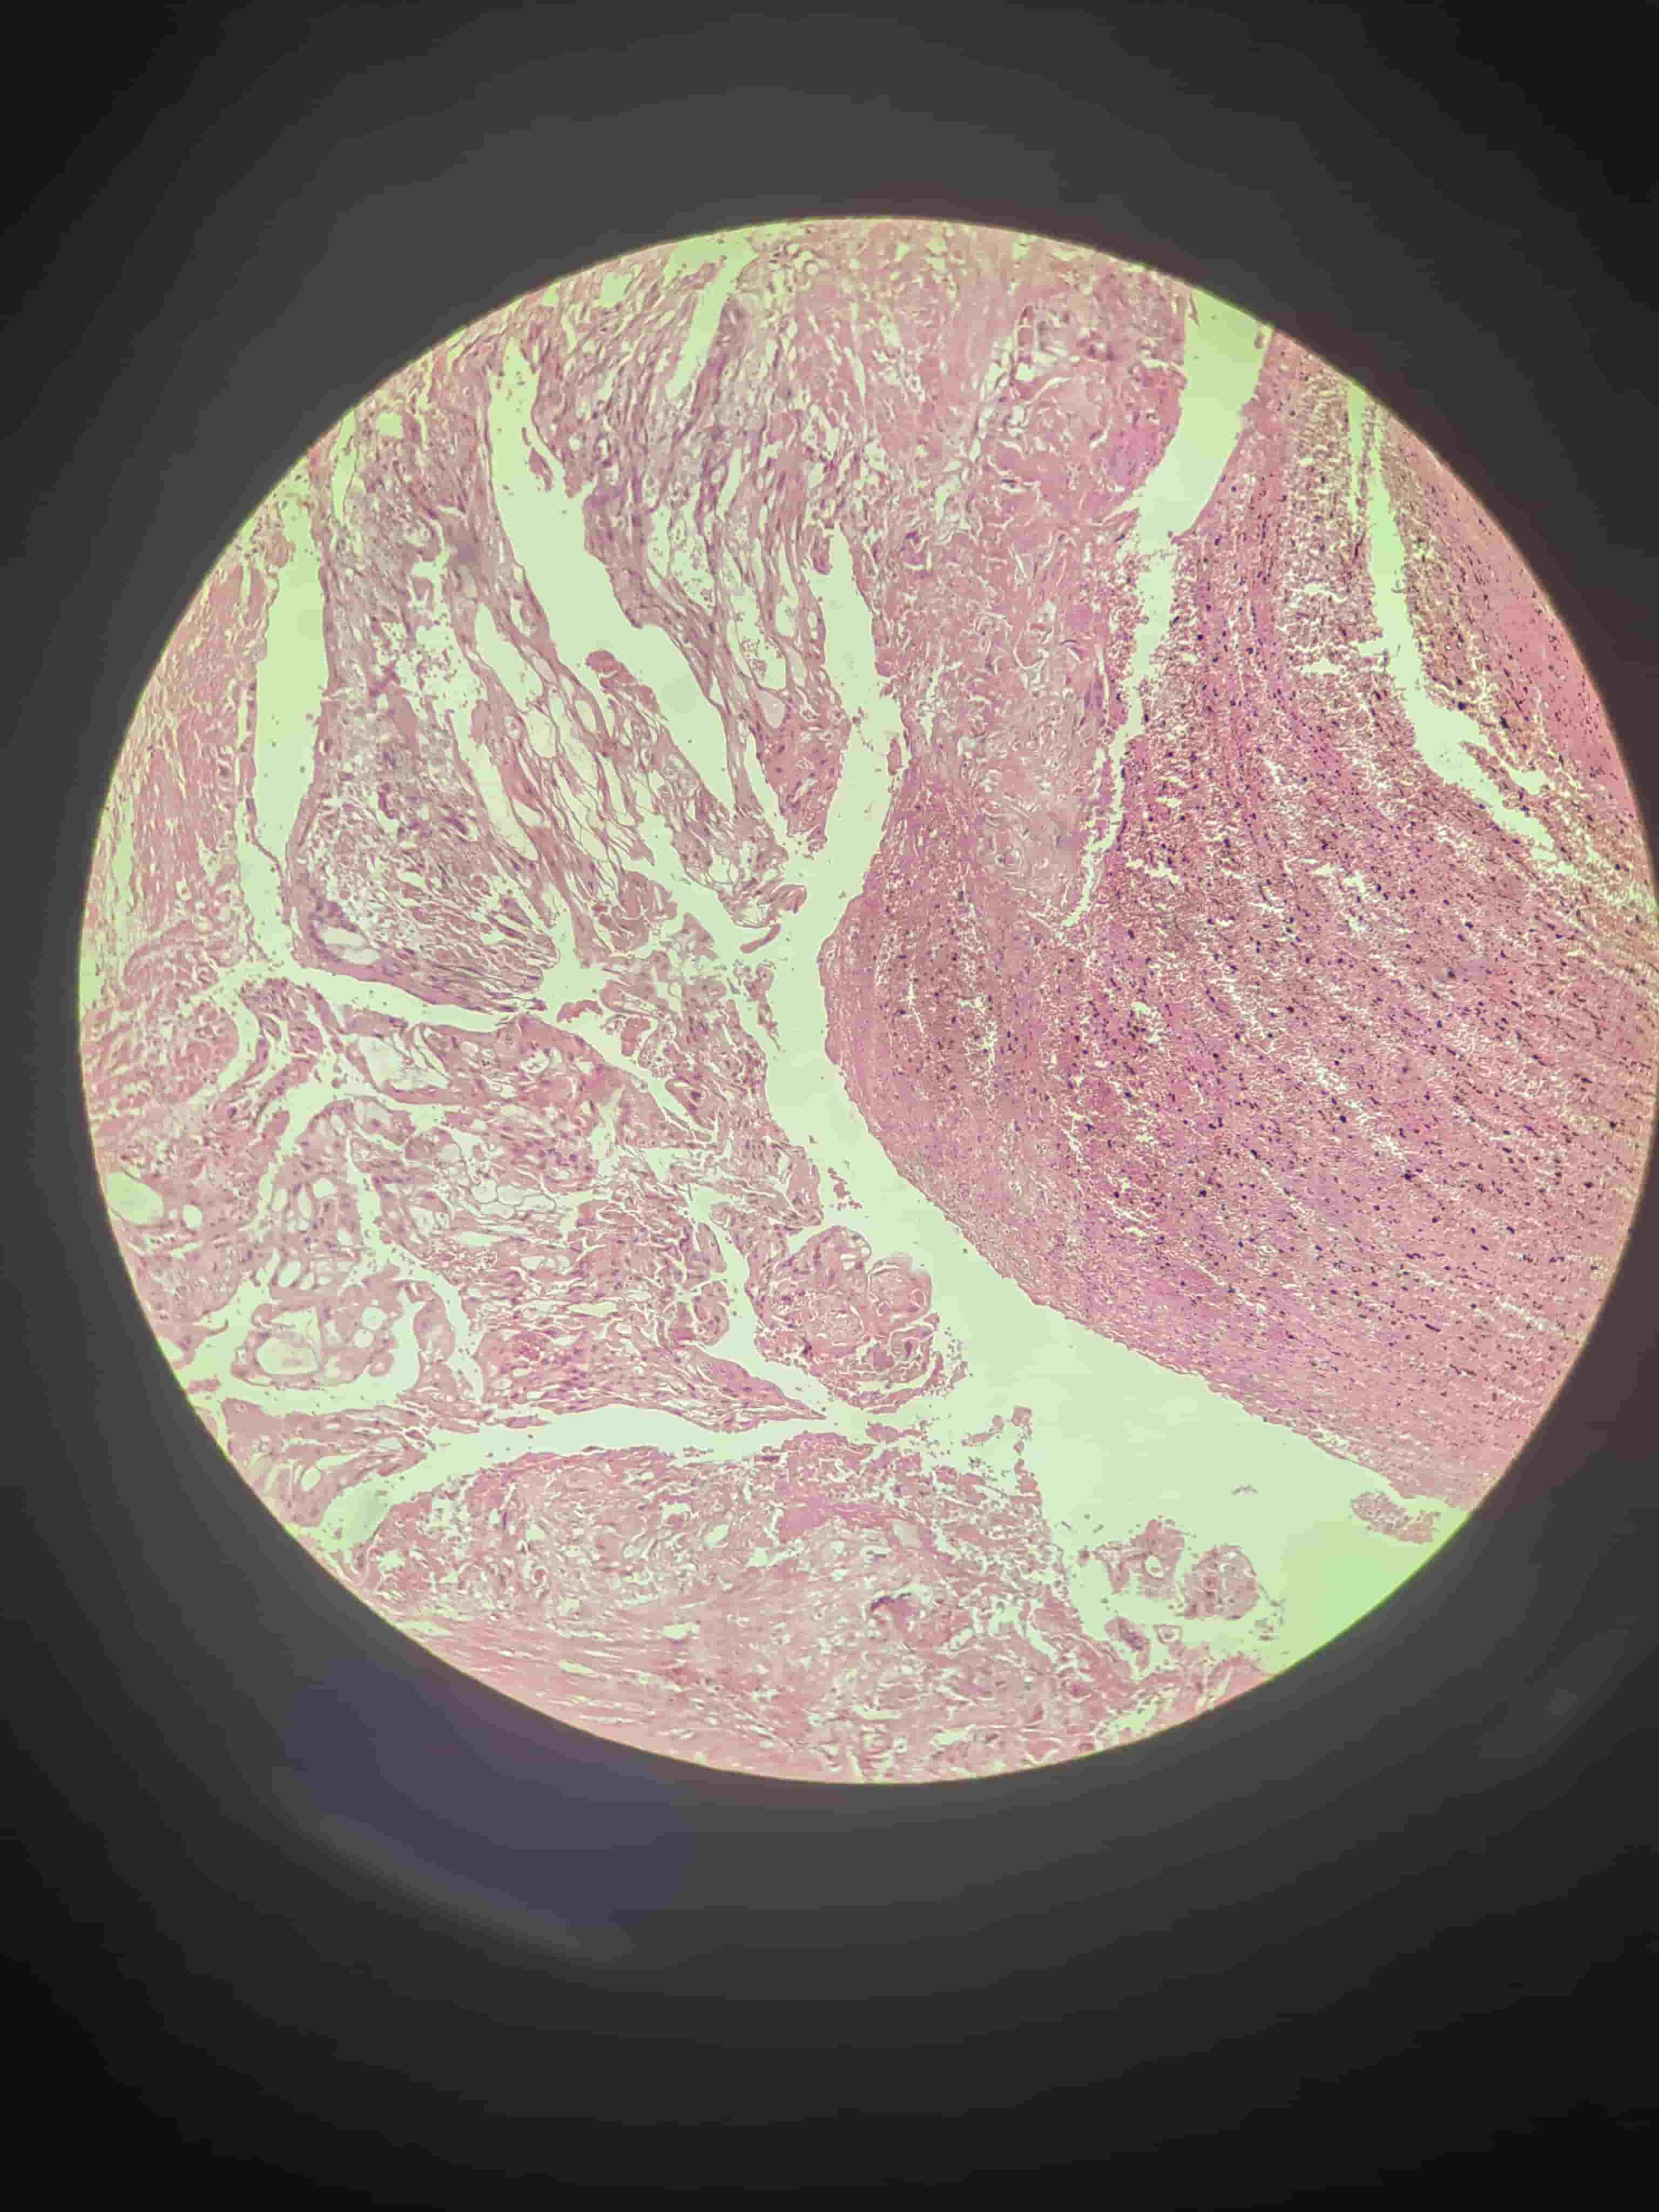

慢性胃溃疡

纤维素性心外膜炎